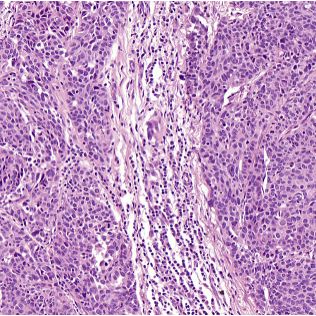

Modeling the Tumor Microenvironment

The tumor microenvironment remains a major limitation in predictive drug testing, especially when assessing compound efficacy early in development. MIMETAS addresses this blind spot by integrating key components into a single perfused system.

- Tumor-associated fibroblasts

Tumor-Stroma- Macrophage Interaction